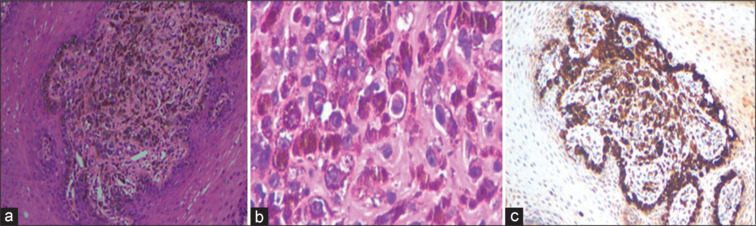

Mucosal melanomas (MMs) represent a rare subset of melanomas arising from melanocytes in noncutaneous sites such as mucosal membranes of the head-and-neck, gastrointestinal, and genitourinary tracts. Unlike cutaneous melanomas, MMs often present late due to their occult nature, leading to a poor prognosis. Fluorine-18 fludeoxyglucose positron emission tomography/computed tomography (18F-FDG PET/CT) is widely utilized for staging and monitoring melanomas, leveraging their characteristic high FDG avidity. Recently, fibroblast activation protein inhibitor (FAPI)-based PET/CT imaging has become a popular modality in the evaluation of various cancers. Here, we present a case of MM where FDG avidity was notably absent and mild FAPI avidity, despite the lesion's typical anatomical location and clinical suspicion. This case highlights an uncommon scenario within the literature and underscores the variability in radiotracer uptake observed in MMs, challenging conventional imaging expectations and potentially impacting clinical management decisions.

Abstract Image